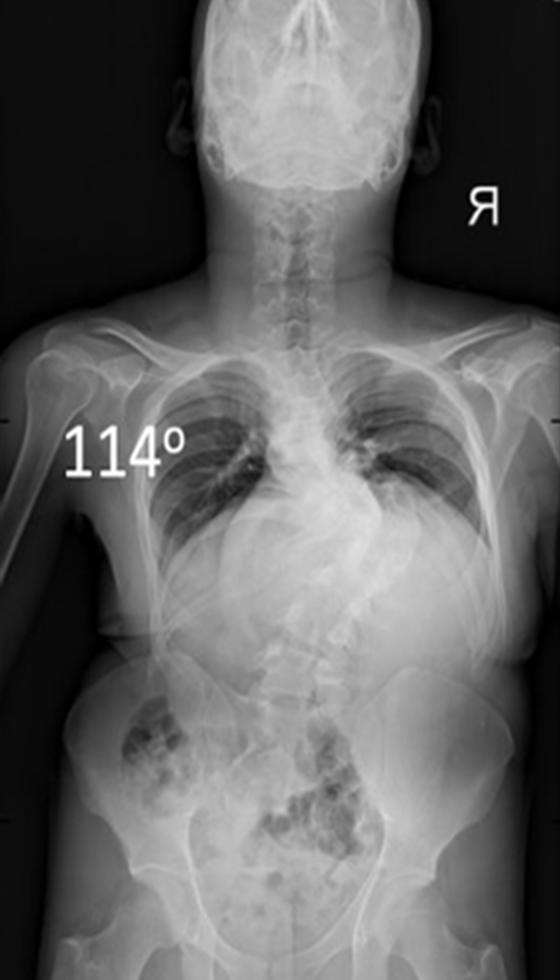

Gallery : Before - After